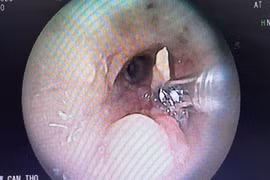

Hy hữu: Hóc xương vịt trong phế quản 2 năm mới gắp ra

Sau khi lấy mảnh xương vịt ra khỏi phế quản, bệnh nhân mới nhớ lại cách đây khoảng 2 năm có hóc xương và khoảng 1 năm trở lại đây, ông bị ho dai dẳng, đau ngực kéo dài, viêm phổi nặng tái phát nhiều lần.